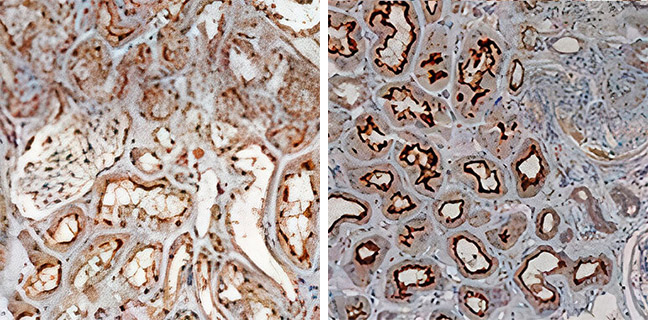

A gray sticky mucus has clogged your blood sugar drain.

And yet, as you read this, a gray sticky mucus is blocking up your drain.

This clog is sending sugar back into your blood. It pushes your blood sugar levels higher.

A little-known ‘gray sticky mucus’ is clogging up their body’s Blood Sugar Drain.

Excess sugar should get drained. But instead, that clog sends it right back to your bloodstream. Your blood sugar levels go sky high.